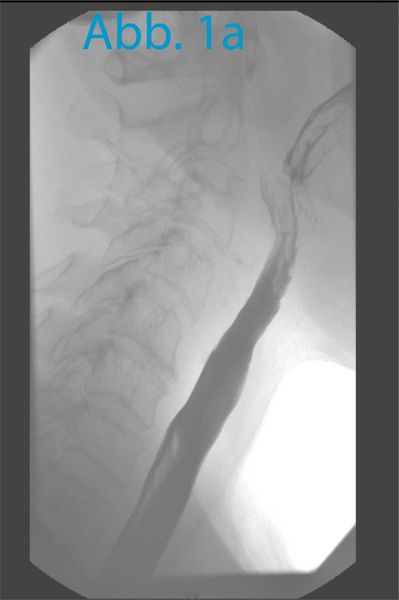

Zur genauen Darstellung des spastischen Pharynxsegmentes (Das „spastische Pharynxsegment“ ist eigentlich ein zirkulär kontraktionsfähiger Anteil des M. constrictor pharyngis) wird nun eine Videokinematographie des Schluckaktes und während eines Sprechversuches durchgeführt. Hierfür wird zunächst in Frontal- und Lateraldurchleuchtung ein Schluck bariumhaltiges Kontrastmittel geschluckt um hochgradige Pharynxstenosen auszuschließen (Bild 1a). Die Schleimhaut des Pharynx ist nun für einige Minuten röntgenkontrastiert. In Seitprojektion erfolgt der Sprechversuch. Hierfür wird der Oberrand des Tracheostomas mit einem röntgendichten Marker (z.B. Büroklammer) markiert. Dann verschließt der Patient manuell sein Tracheostoma und versucht mit Kraft „AAA“ zu sagen. Während diesem Versuch erfolgt die Durchleuchtung. Es zeigt sich typischerweise ein Bild, auf dem das spastische Pharynxsegment sichtbar ist, wie in Abbildung 1b dargestellt. Es kann nun der Abstand zwischen Tracheostomaoberrand (Marker) und spastischem Pharynxsegment ausgemessen und am Patienten angezeichnet werden wie in Abb. 2 demonstriert.